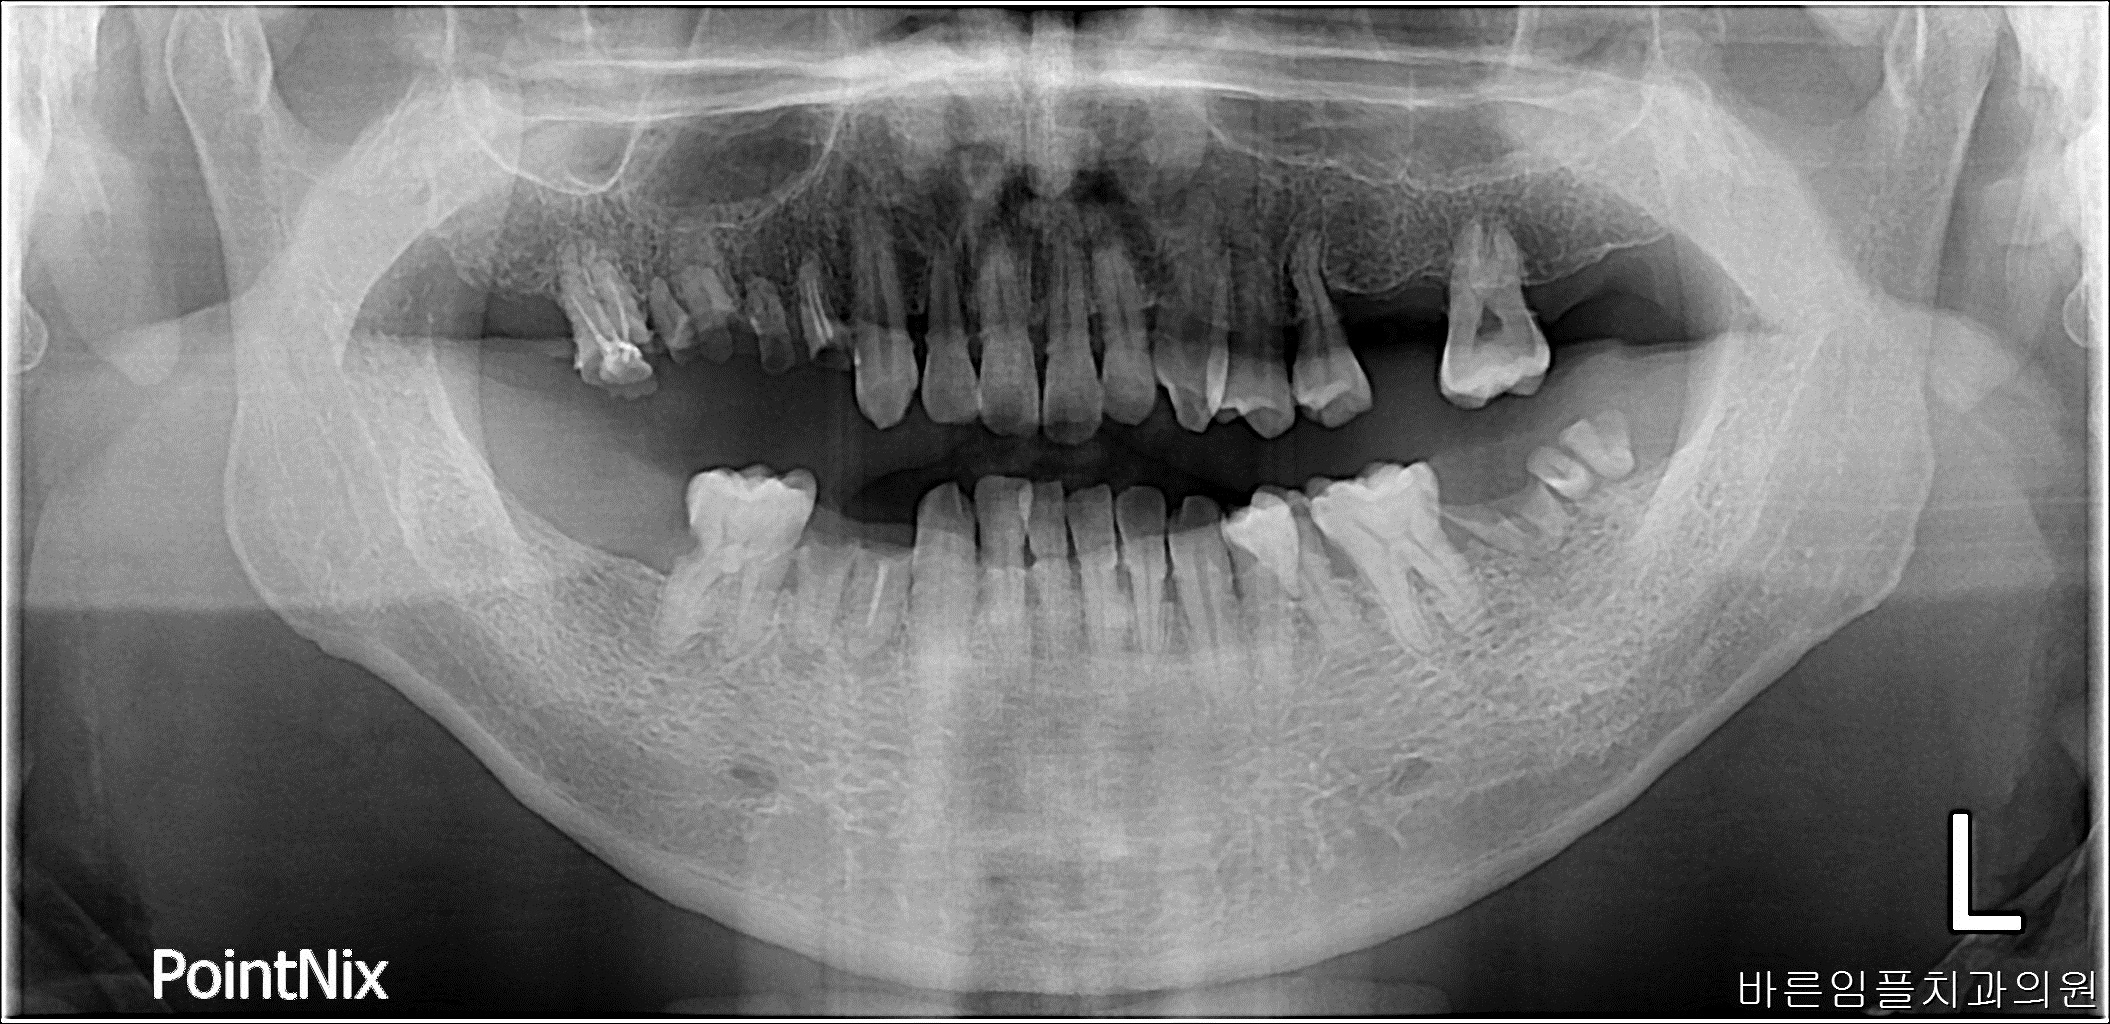

박ㅇㅇ / 수면임플란트 페이지 정보 작성일 23-10-27 17:02 2023-04-20 박ㅇㅇ Before 2023-09-07 박ㅇㅇ After 박ㅇㅇ / 수면임플란트 목록 이전글이ㅇㅇ / 수면임플란트 다음글 남ㅇㅇ / 임플란트